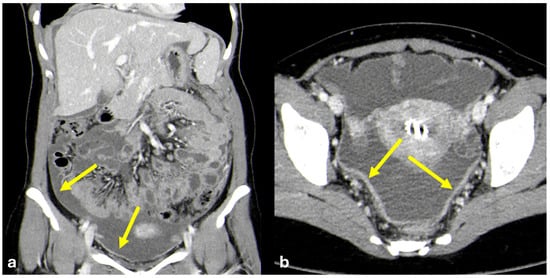

- Nodular pattern: nodules with a diameter > 5 mm (Figure 2a);

- “Omental cake”: nodular thickening of the omentum (Figure 2b);

- Plaque pattern: confluent nodular plaques, typically involving the lower surface of the right diaphragm (Figure 3);